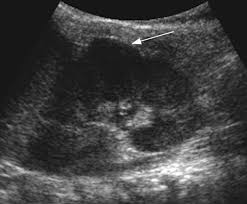

46 years experience internal medicine. Dromedary hump is a prominent focal bulge on the lateral border of the left kidney caused by splenic impression, which can mimic renal neoplasm. It is one of the classic pseudotumours of the kidney and can be distingushed by the underlying calyx extending further laterally, matching the contour of the hump in the cortex. About press copyright contact us creators advertise developers terms privacy policy & safety how youtube works test new features press copyright contact us creators. Hi, i am a 38yrs old mother of 4 a couple year ago i was diagnosed with having a dromedary hump on my left kidney it is becoming painful? Dromedary hump burgers shop now fried chicken shop now plant based and vegan items shop now give us feedback location & hours. 2), but also can be seen with. Dromedary camels are the tallest.

Dromedary hump appears as a focal bulge on the lateral border of the left kidney, caused by molding of the normal renal parenchyma by the adjacent spleen. A dromedary has one hump, long limbs and short hair. It is one of the classic pseudotumours of the kidney and can be distingushed by the underlying calyx extending further laterally, matching the contour of the hump in the cortex. Dromedary hump and bertini columns are two of the renal pseudotumors. Dromedary camels live in hot climates. = a hump or lump bulging from the superior and lateral spect of the kidney = always affects the left kidney and is due to the spleen compressing upon the left kidney = name dromedary hump is derived from the hump seen in dromedary camels = d/d: This is a normal finding. Since this looks like camel's hump on the film, this is called dromedary hump. Care should be taken as it can be mistaken for a renal mass. The incidence of this normal anatomic variant is estimated to be about 0.5%.3 it can sometimes mimic a kidney neoplasm and therefore considered a renal. 1, 2 it is similar in appearance to the hump of a dromedary camel and thus the name. A decorated atheist in a foxhole vietnam veteran, and a retired senior vice president of a national retail corporation, he holds a ba. Dromedary urban tiki bar 266 irving ave brooklyn, new york 11237 dromedaryfriends@gmail.com.

The main difference between a camel and dromedary lies in the number of humps they have on their back. Dromedary camels are the tallest. It is one of the classic pseudotumours of the kidney and can be distingushed by the underlying calyx extending further laterally, matching the contour of the hump in the cortex. For instance, the length and thickness of their fur differ. It is usually created by the pressure of surrounding organs to the cortex of the kidney during development. Dromedary hump appears as a focal bulge on the lateral border of the left kidney, caused by molding of the normal renal parenchyma by the adjacent spleen.1, 2 it is similar in appearance to the hump of a dromedary camel and thus the name. The incidence of this normal anatomic variant is estimated to be about 0.5%.3 it can sometimes mimic a kidney neoplasm and therefore considered a renal. The dromedary hump (dh) is marked along the lateral border. The bactrian lives in cold climates. Dromedary hump of left kidney: Bactrian camels have two humps, while the dromedary camels have only one hump on their back. On june 4, 1855, major henry c. Dromedary hump is a radiological term for normal kidney tissue molded by the adjacent organs.

Dromedary humps are important because they may mimic a renal mass, and as such is considered a renal pseudotumor. Dromedary hump of left kidney: The term dromedary hump or splenic hump refers to a bulge in the middle of the lateral surface of the left renal cortex. For instance, the length and thickness of their fur differ. Apart from the differences in the number of humps, there are other notable differences too. The main difference between a camel and dromedary lies in the number of humps they have on their back. This is most commonly seen in the left kidney caused by the spleen. Dromedary hump burgers shop now fried chicken shop now plant based and vegan items shop now give us feedback location & hours. It is usually created by the pressure of surrounding organs to the cortex of the kidney during development. Kidneys of position, dimensions and parenchymal thickness within normality, identifying nodular image hypodense and heterogeneous in the anterior cortical of the. Dromedary hump is a prominent focal bulge on the lateral border of the left kidney caused by splenic impression, which can mimic renal neoplasm. The hump stores up to 80 pounds of fat, which a camel can break down into water and energy when. Bactrian camels are the largest.

Dromedary hump appears as a focal bulge on the lateral border of the left kidney, caused by molding of the normal renal parenchyma by the adjacent spleen1, 2 it is similar in appearance to the hump of a dromedary camel and thus the name drome. Since this looks like camel's hump on the film, this is called dromedary hump.